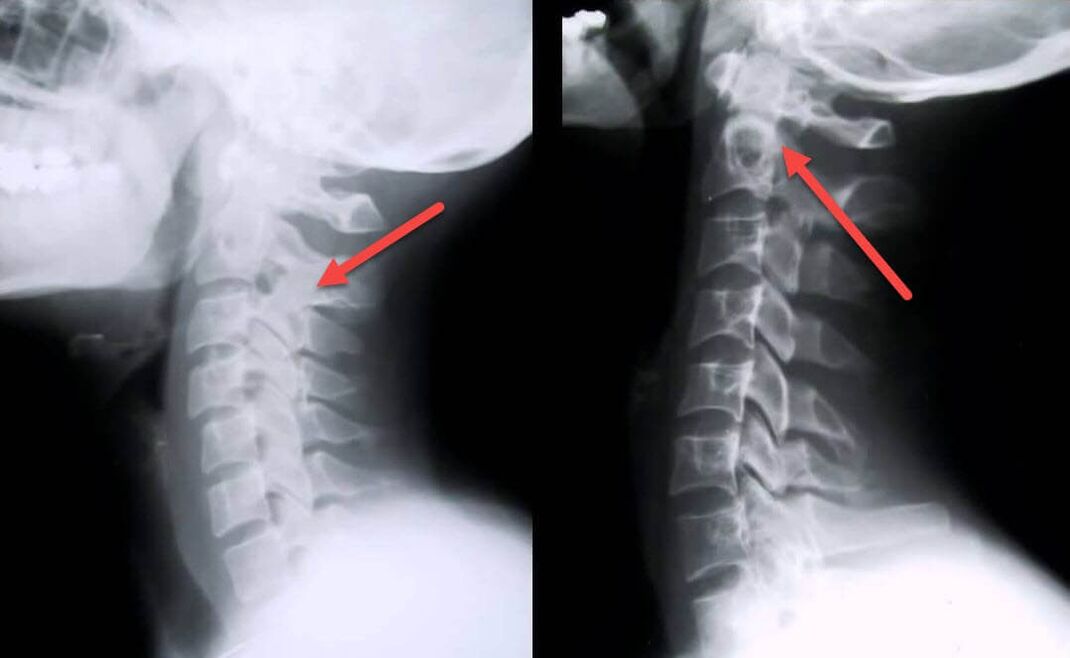

O procedimento diagnóstico mais informativo é a radiografia. As patologias de 1º grau correspondem ao 1º ou 2º estágio radiológico. As imagens resultantes visualizam sinais típicos da doença.

| Estágios radiográficos da osteocondrose cervical de 1º grau | Sinais característicos |

|---|---|

| Estágio 1 | Pequenas alterações na curvatura da coluna vertebral na região cervical, afetando um ou mais segmentos |

| Estágio 2 | Ligeiro espessamento dos discos intervertebrais, deformação dos processos uncinados, endireitamento da lordose, pequenos crescimentos das estruturas ósseas |